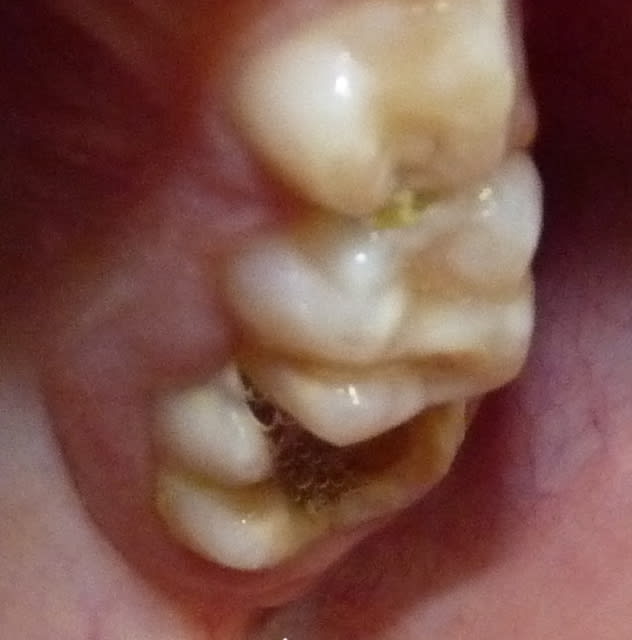

Vu cet après-midi : 26 délabrée par MIH et manque hygiène incluse sous 65. La maman consulte car ne veut pas enlever la dent, OK pour le HN.

Je vais avulser 65, cureter, mettre un MTA et un CVI, attendre 1 mois pour avoir un peu d'egression et faire ma CPP. Il faudra ensuite probablement un passage chez l'ortho pour redresser l'axe.